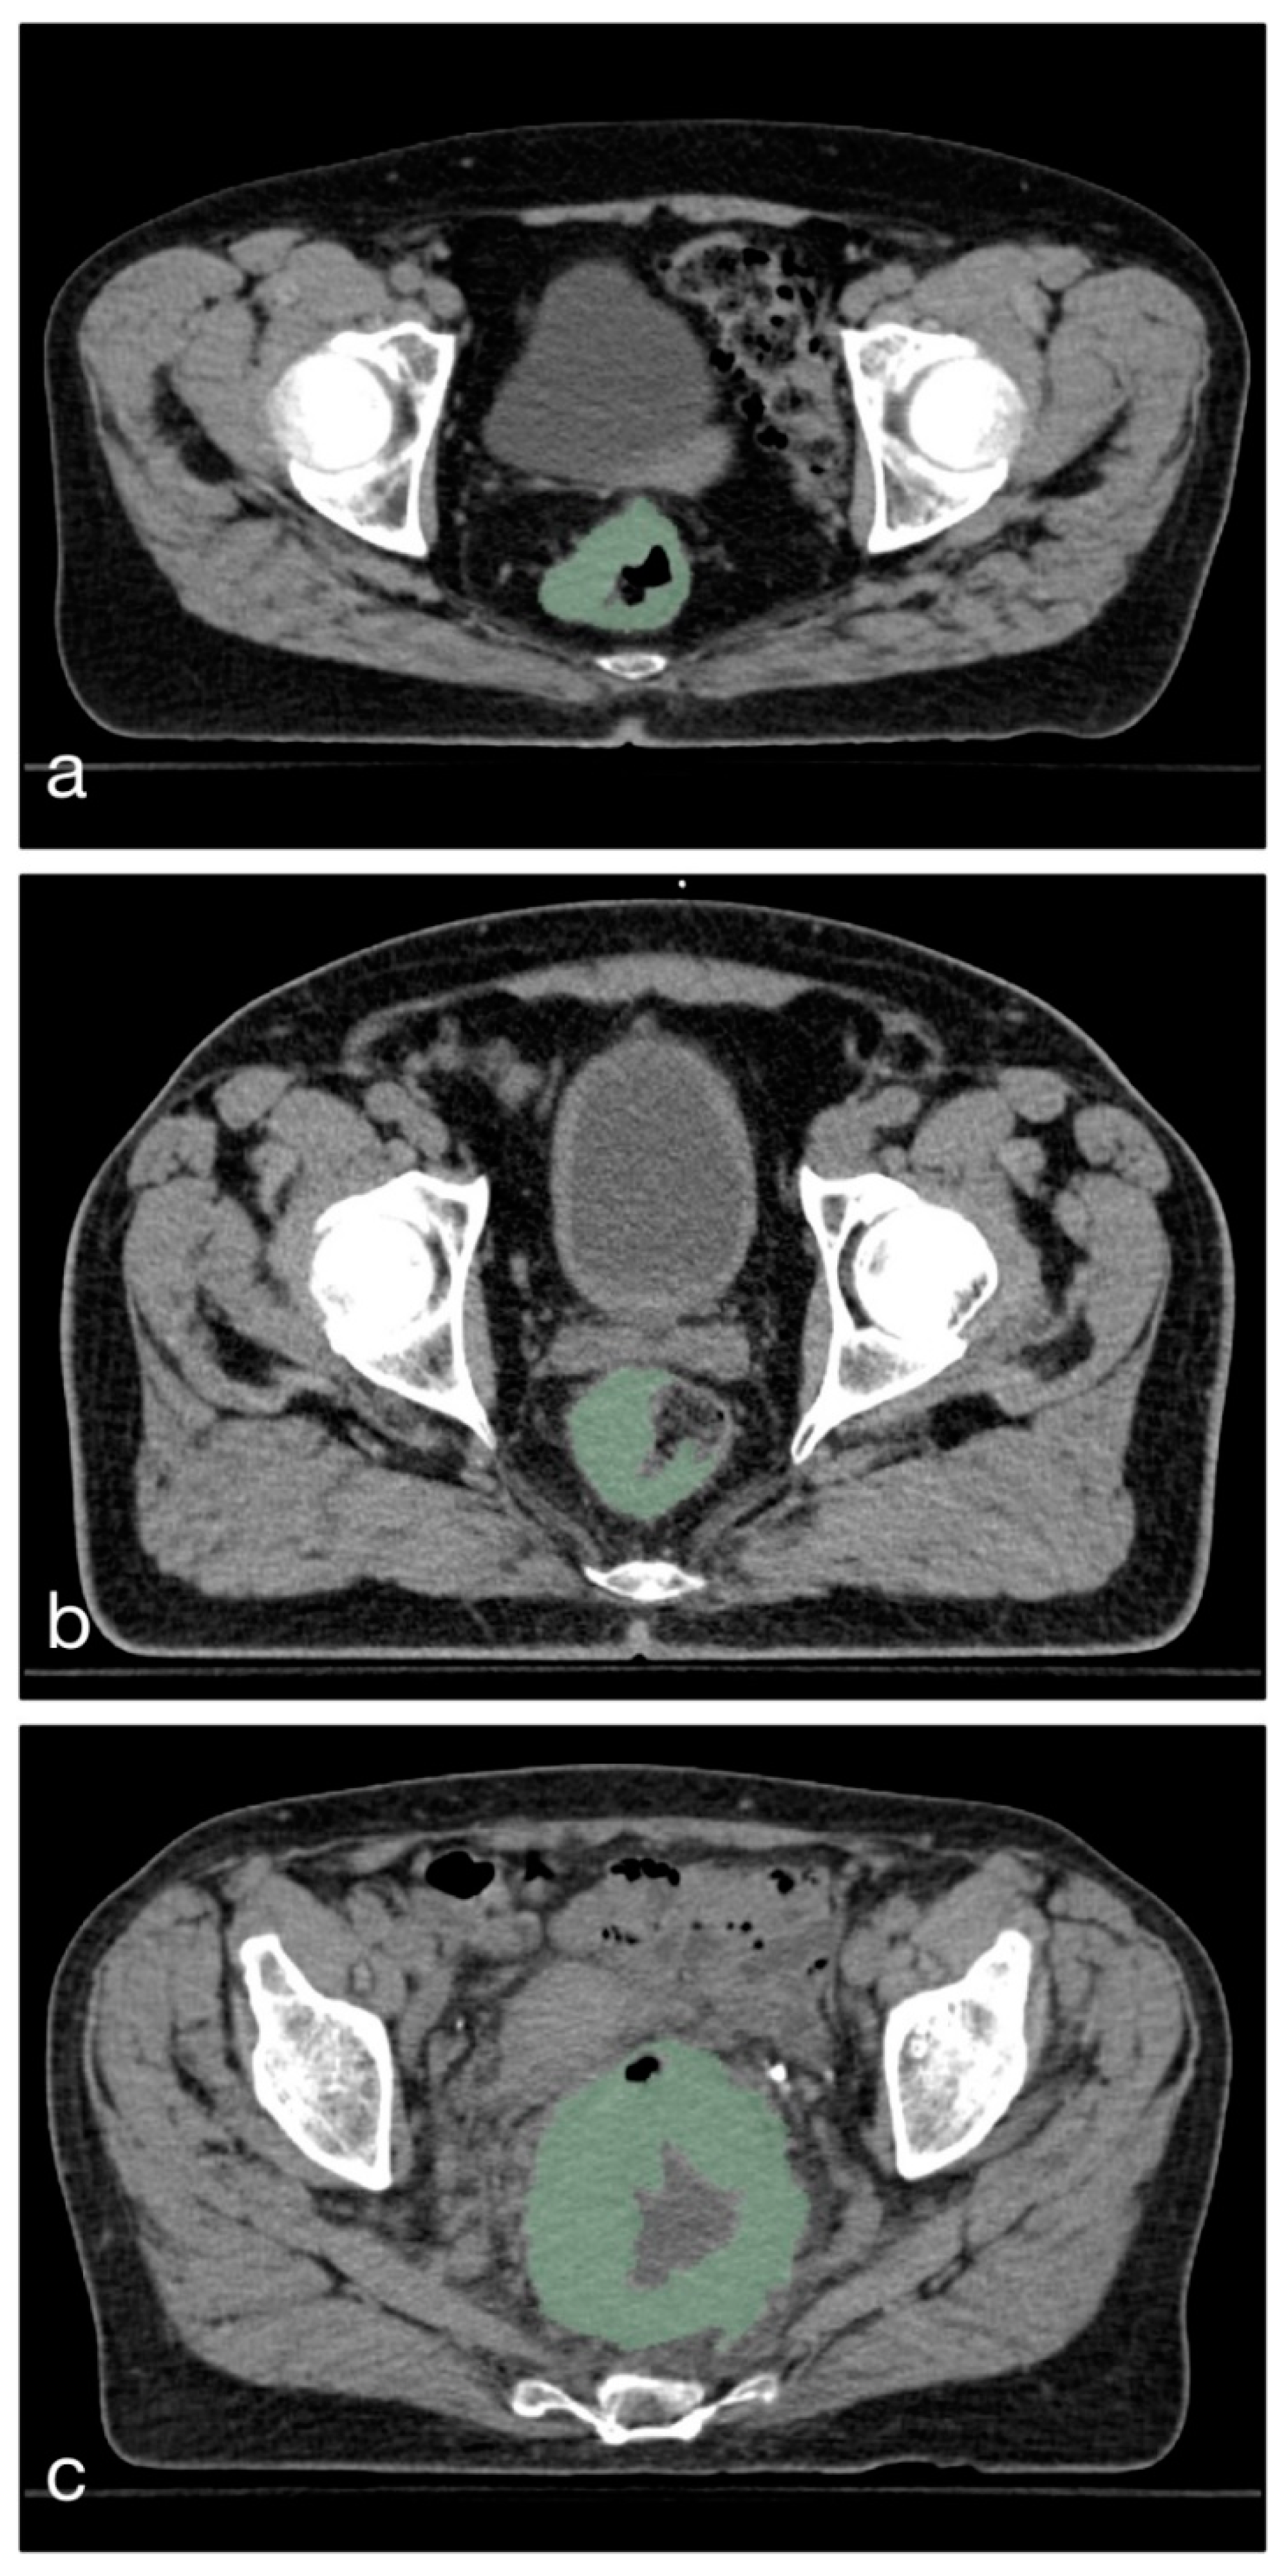

2.1. Patients and Imaging

4. Materials and Methods

4.2. Dataset Composition

| Scanner | Siemens Emotion (16 Slices) |

| Acquisition matrix | 512 × 512 |

| Voxel size | 0.98 × 0.98 × 3 mm |

| Dose Modulation | None |

| Convolution Kernel | B40s |

| Contrast Agent | Non-contrast |